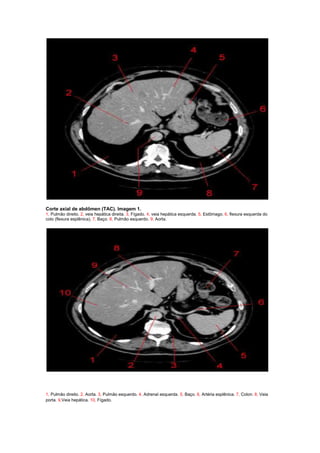

Corte axial de abdômen (TAC). Imagem 1.

1, Pulmão direito. 2, veia hepática direita. 3, Fígado. 4, veia hepática esquerda. 5, Estômago. 6, flexura esquerda do

colo (flexura esplênica). 7, Baço. 8, Pulmão esquerdo. 9, Aorta.

1, Pulmão direito. 2, Aorta. 3, Pulmão esquerdo. 4, Adrenal esquerda. 5, Baço. 6, Artéria esplênica. 7, Colon. 8, Veia

porta. 9,Veia hepática. 10, Fígado.

Corte axial de abdômen (TAC). Imagem 4

1, Veia cava inferior. 2, Fígado. 3, Adrenal direita. 4, Pilar do diafragma. 5, Aorta abdominal. 6, Adrenal

esquerda. 7, Rim esquerdo. 8, Baço. 9, Pâncreas. 10, Colon.

Corte axial deabdômen (TAC). Imagem 1. 1, Pulmão direito. 2, veia hepática direita. 3, Fígado. 4, veia hepática esquerda. 5, Estômago. 6, flexura esquerda do colo (flexura esplênica). 7, Baço. 8, Pulmão esquerdo. 9, Aorta. 1, Pulmão direito. 2, Aorta. 3, Pulmão esquerdo. 4, Adrenal esquerda. 5, Baço. 6, Artéria esplênica. 7, Colon. 8, Veia porta. 9,Veia hepática. 10, Fígado.

Corte axial deabdômen (TAC). Imagem 3 1, Diafragma. 2, Aorta. 3, Adrenal esquerda. 4, Pólo superior do rim esquerdo. 5, Baço. 6, Artéria esplênica. 7, Colon. 8, Estômago. 9,Veia porta. 10, Fígado. 11, Costela. Corte axial de abdômen (TAC). Imagem 4 1, Veia cava inferior. 2, Fígado. 3, Adrenal direita. 4, Pilar do diafragma. 5, Aorta abdominal. 6, Adrenal esquerda. 7, Rim esquerdo. 8, Baço. 9, Pâncreas. 10, Colon.